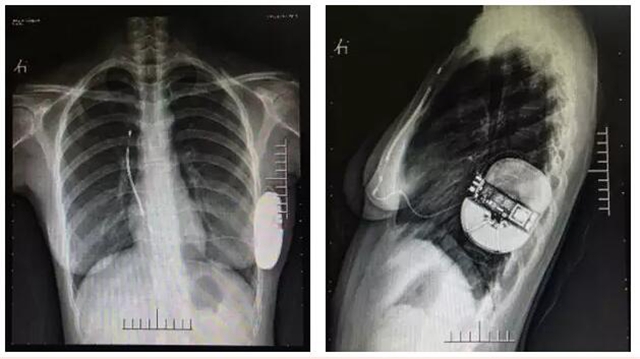

术后X线影像

叶强介绍,全皮下植入式心律转复除颤器这项技术是在心脏性猝死预防领域取得革命性突破的新技术。它能够提供与传统心律转复除颤器相同的预防心脏骤停的治疗。但它的整个系统只植入于皮下,不直接接触心脏和血管,能够彻底杜绝可能的血管损伤、减少潜在的系统感染风险,保留静脉通路,避免经静脉导线植入或拔除的相关并发症。